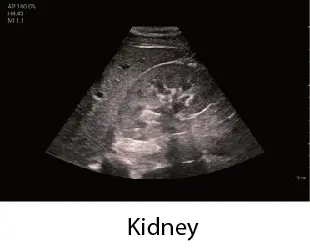

Чрез интегриране на множество приложения, TE Air e5M предлага сканиране на цялото тяло и се адаптира към различни клинични ситуации. Неговият безжичен дизайн осигурява възможност за извършване на ултразвукови изследвания с високо качество по всяко време и навсякъде. Освен своята универсалност, TE Air e5M предлага и редица интелигентни функции и обучителни инструменти, които повишават увереността и ефективността при работа.

Сканирайте цялото тяло с увереност

Абдомен, малки част, съдови, акушерство, гинекология, FAST и др

"как" и "какво" при извършване на ултразвукови изследвания. Включва анатомични илюстрации, стандартни ултразвукови изображения, референтни снимки за сканиране и съвети за умело извършване на диагностика. Обхваща приложения за корем, щитовидна жлеза, съдова система, малки части, урология, акушерство и гинекология, FAST протоколи, кардиология и нервна система.

Клинични снимки